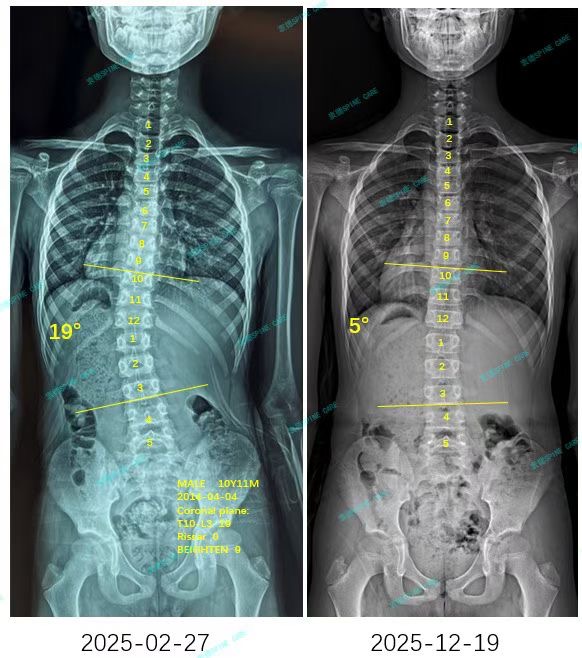

来自家长对衷德的评价(QQ妈妈)

衷德脊柱,我们只关注侧弯保守治疗~

Zhongde Spine, bending no breaking ~